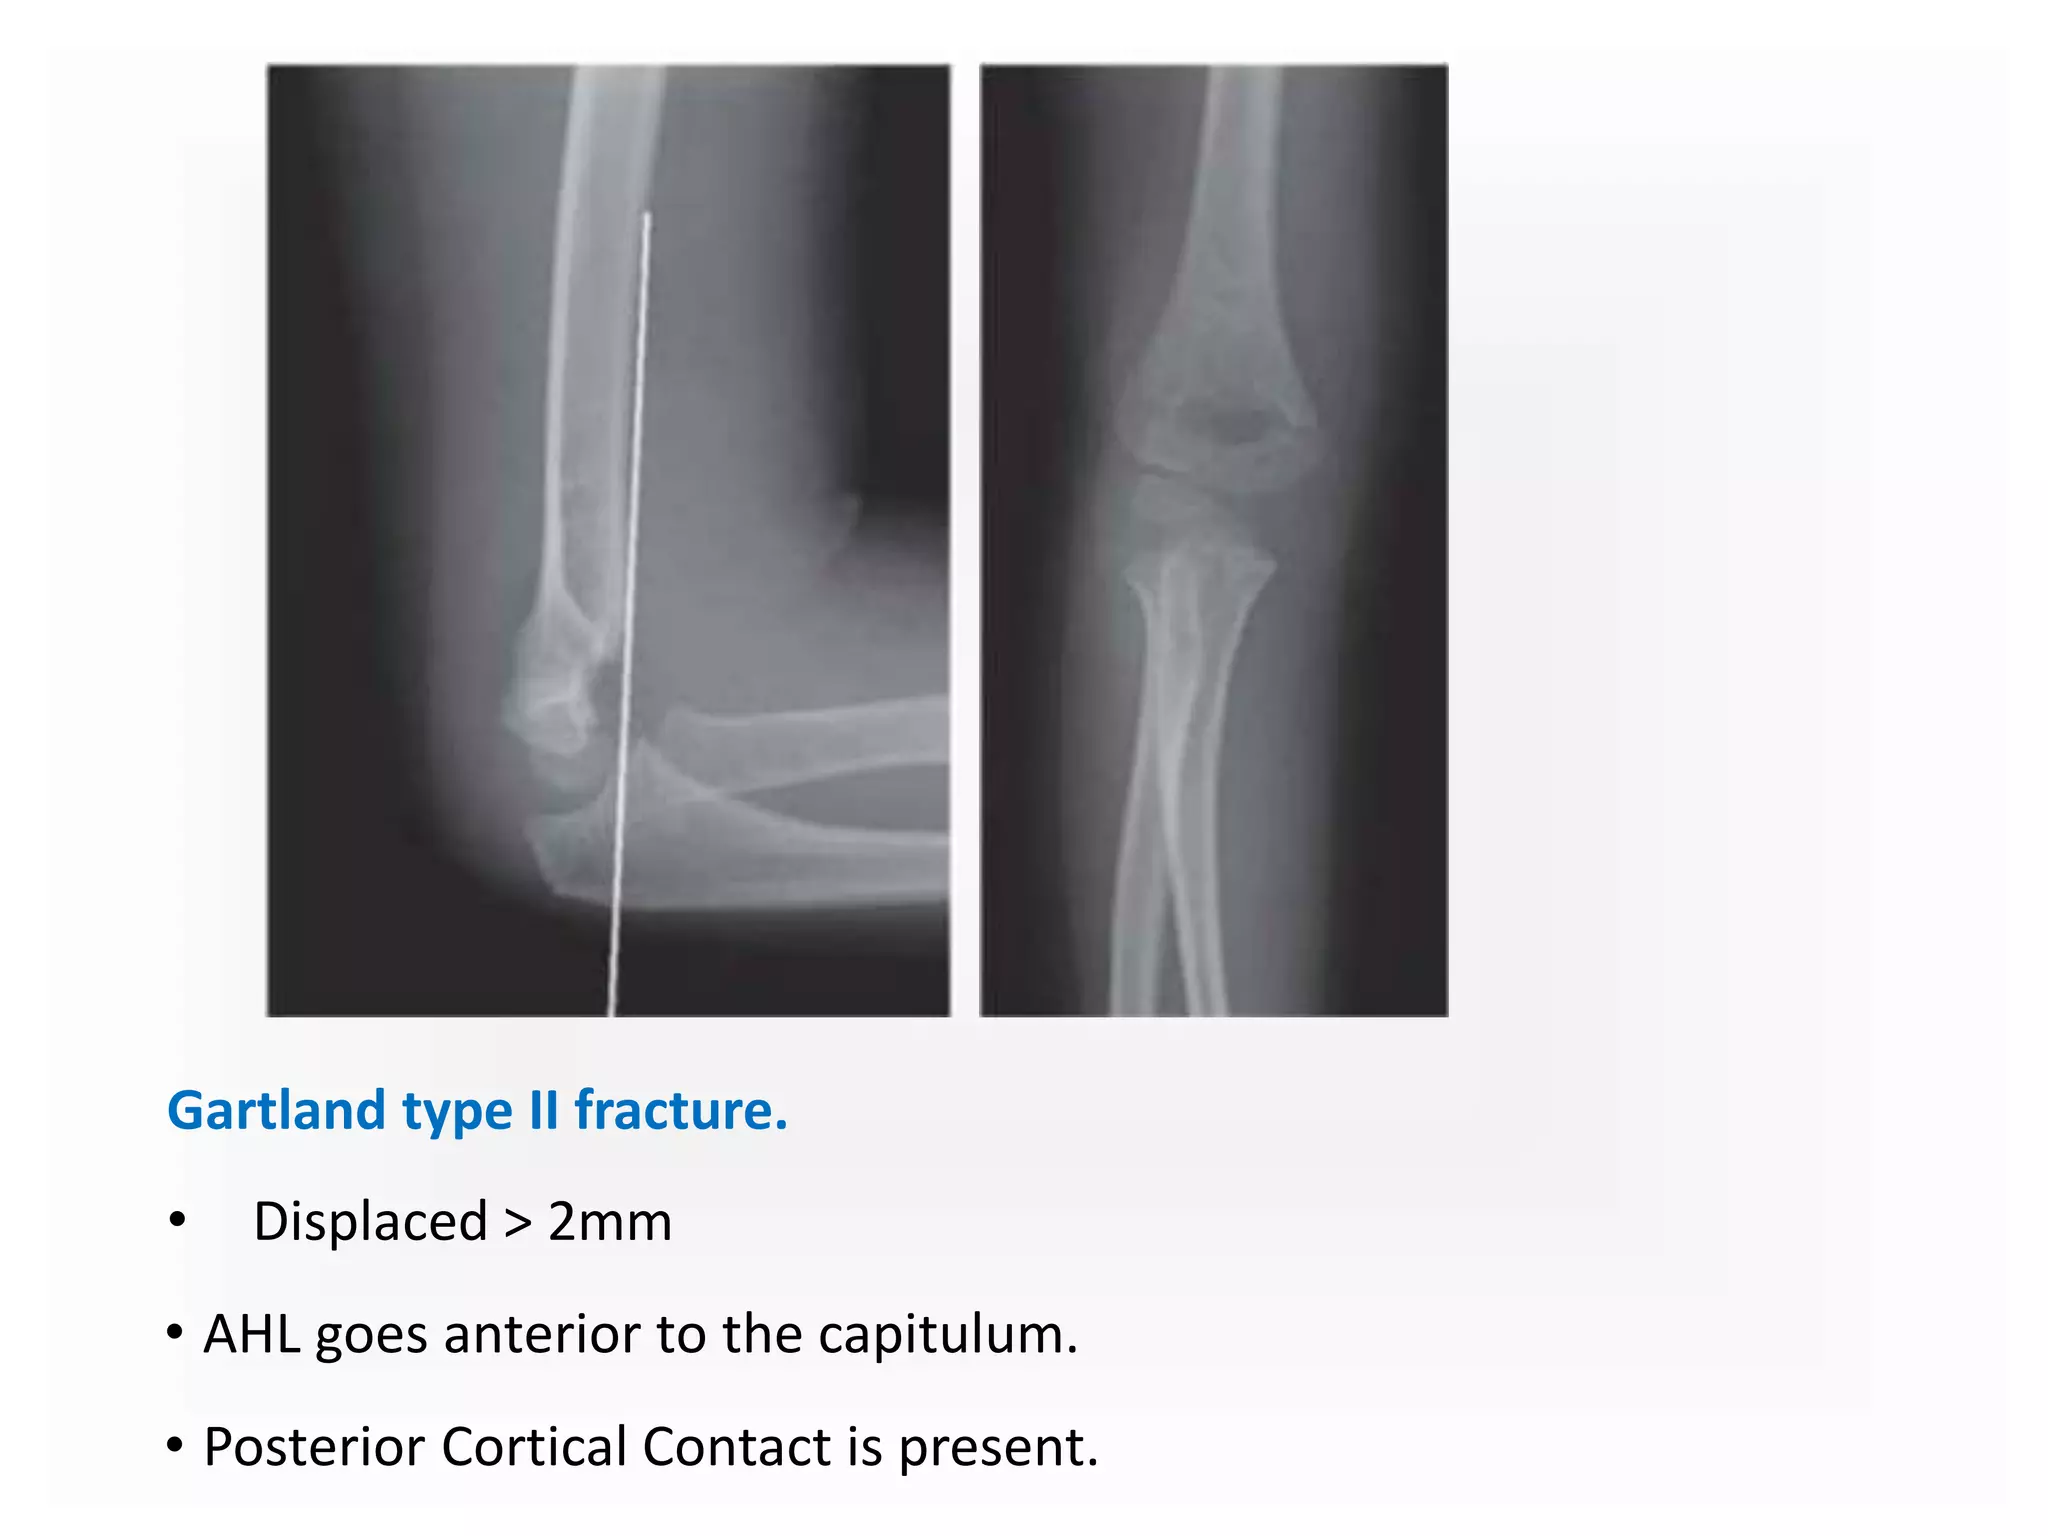

Gartland type II fracture.

• Displaced > 2mm

• AHL goes anterior to the capitulum.

• Posterior Cortical Contact is present.